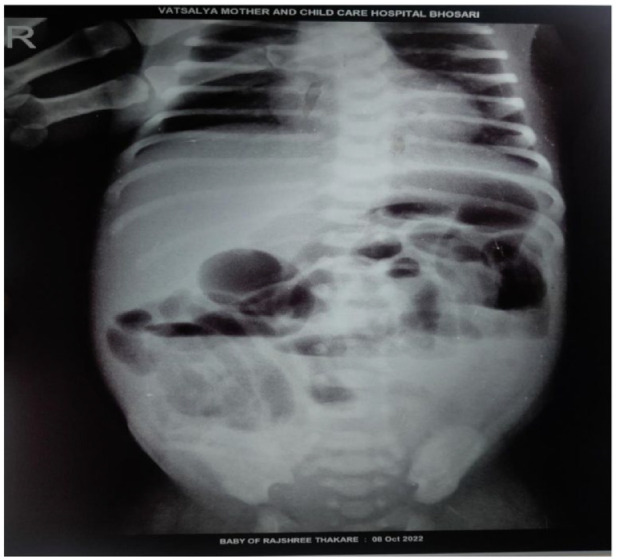

赫氏病是一种先天性疾病,其特点是结肠肌肉神经细胞缺失,导致排便困难。本病例报告描述了一名新生儿患者的典型症状,包括腹胀、便秘、腹泻和发热。患者最初的实验室检查结果显示贫血(血红蛋白:9.80 g/dL)、红细胞计数低(350 万/立方毫米)、RDW 升高(16.70%)、白细胞计数升高(11 000/立方毫米)、血小板水平升高(891 000/微升)以及 CRP 升高(3.22)。婴儿接受了综合治疗,包括输血、Syp.MVBC, Enterogermina, Inj.Pan, Inj.Metro、Inj.Piptaz, Inj.万古霉素、葡萄糖酸钙和 Inj.阿米诺文。经过治疗和必要的手术干预后,患者频繁排便的情况明显改善,其他症状也有所缓解。本病例强调了及时诊断和多学科治疗对婴儿赫氏贲门失弛缓症患者获得良好治疗效果的重要性。

Hirschsprung's disease is a congenital disorder characterized by the absence of nerve cells in the colon muscles, leading to difficulties in evacuating stool. This case report describes a newborn patient presenting with typical symptoms of the disease, including abdominal distension, constipation, diarrhea, and fever. The patient's initial laboratory investigations revealed anemia (Hb: 9.80 g/dL), low RBC count (3.50 million/cu mm), elevated RDW (16.70%), increased WBC count (11 000/cu mm), and raised platelet levels (891 000/µL) along with an elevated CRP (3.22). The baby received a comprehensive treatment regimen, including blood transfusion, Syp. MVBC, Enterogermina, Inj. Pan, Inj. Metro, Inj. Piptaz, Inj. Vancomycin, Calcium gluconate, and Inj. Aminoven. Following this treatment and necessary surgical intervention, the patient demonstrated significant improvement in frequent bowel movements and alleviation of other symptoms. This case highlights the importance of prompt diagnosis and multidisciplinary management for favorable outcomes in infants with Hirschsprung's disease.